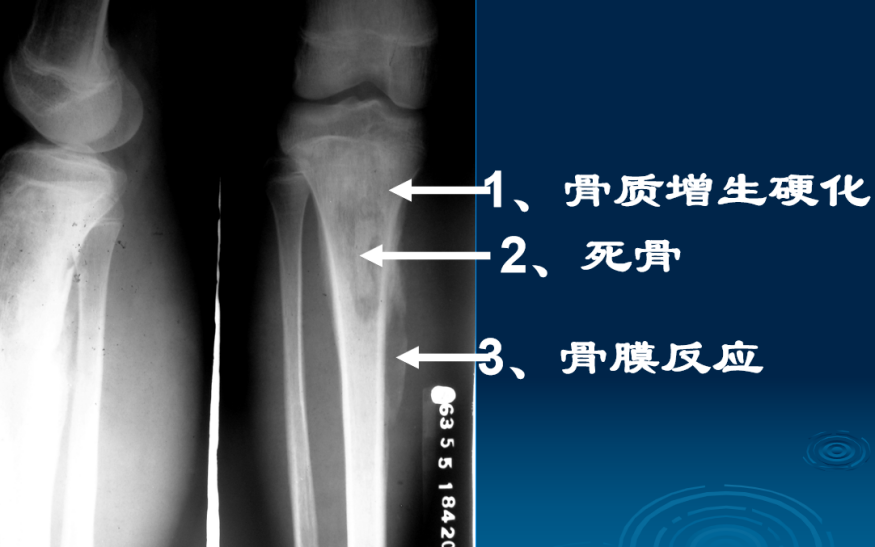

2、慢性化脓性骨髓炎(慢性骨脓肿(Brodie脓肿):由低毒性 葡萄球菌引起,症状轻。干骺端类圆形 破坏区,有硬化边,偶见小死骨,无骨膜增生,硬化性骨髓炎):增生硬化为主、死骨、瘘管

X线平片与CT:1)病变时愈时发,软组织瘘管形成;(2)骨质破坏的同时,以增生硬化为主;骨干增粗,髓腔闭塞,骨膜增生(形成骨壳),死骨仍存(3)愈合:a、破坏区与死骨消失;b、增生硬化吸收,髓腔沟通。

X线表现:1、骨质增生硬化为主。2、骨质破坏轻。3、有脓腔和死骨。4、骨干增粗、变形。5、髓腔变窄甚至闭塞。

慢性硬化性骨髓炎

X线表现

1、骨质增生硬化

2、骨膜增生,髓腔变窄

3、骨干增粗